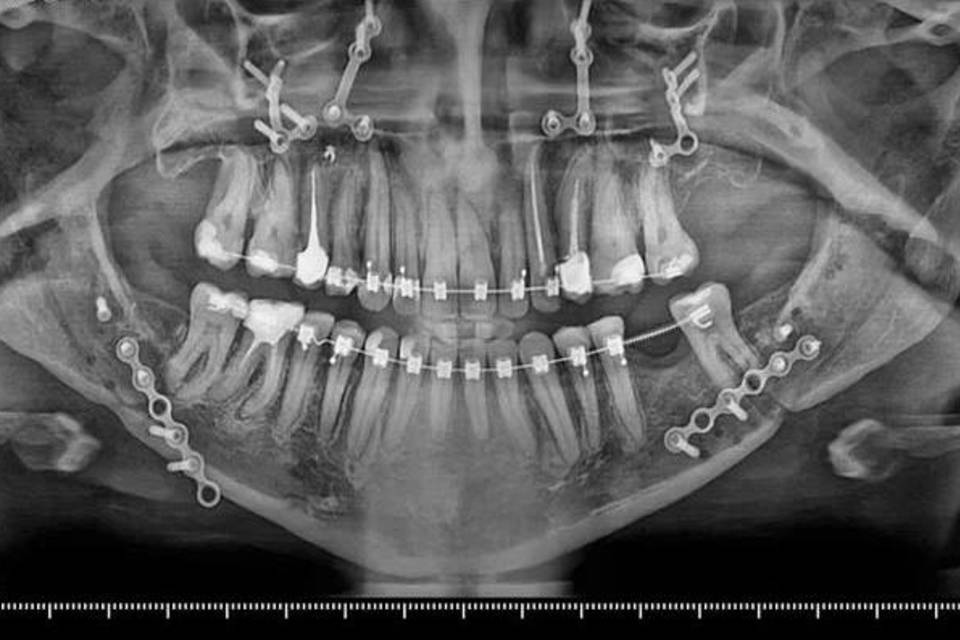

Специалисты городской клинической больницы №1 Волгограда провели первую серию сложнейших операций, сообщают "Городские вести". Первой пациенткой узких специалистов Романа Стасюка и Анастасии Мулиной стала женщина с гнатической формой зубочелюстной аномалии. Пациентка рассказала докторам, что недовольна эстетикой своего лица. Но главное - у нее была нарушена жевательная функция из-за недоразвития верхней челюсти.

В облздраве сообщают, что уже после первого этапа лечения у ортодонта был получен хороший результат. Нормализовалось положение зубов, в порядок пришла координация размеров зубных рядов. После углубленного обследования женщину направили в больницу для проведения операции - двучелюстной остеотомии. Итог оказался очень положительным. Спустя четыре месяца после оперативного вмешательства у пациентки нормализовалась функция жевания, а внешний вид заметно улучшился.